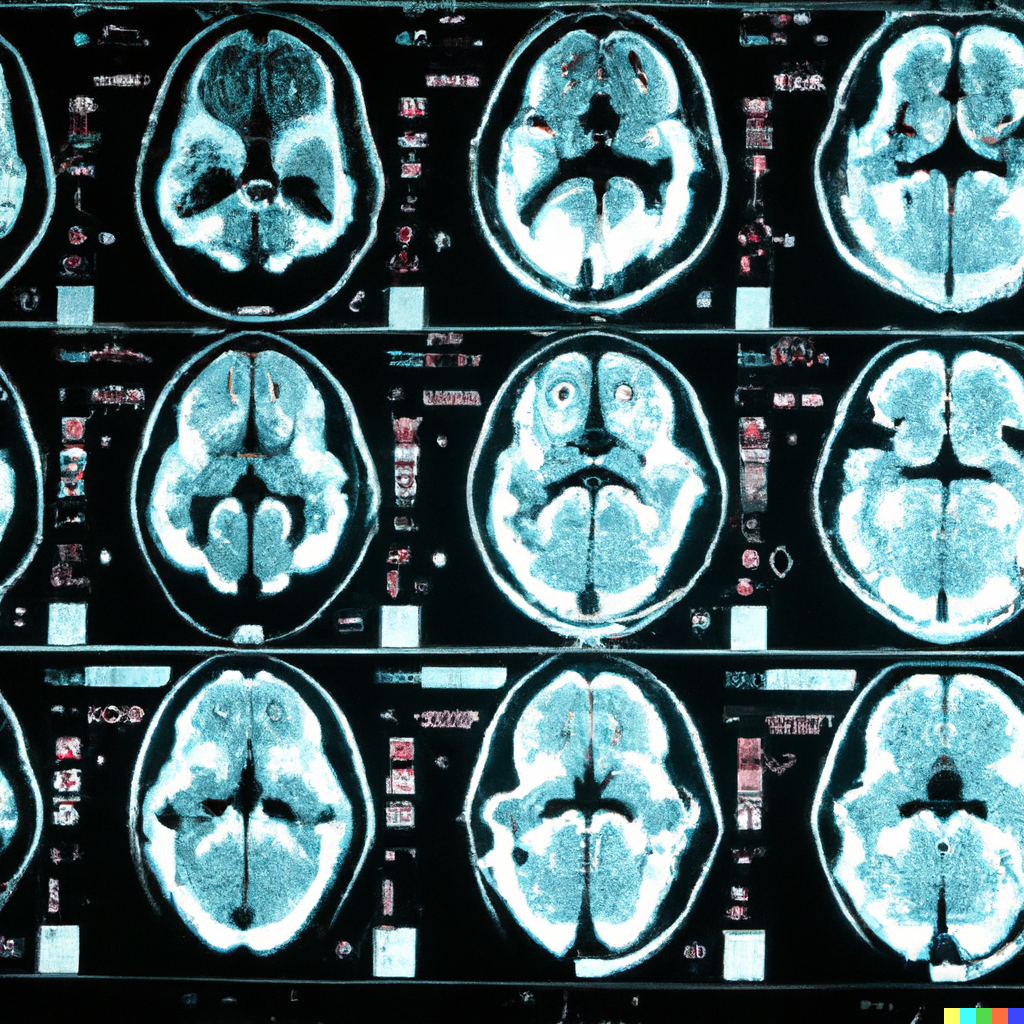

Our tool provides a thorough capture of the MRI suite recording and analysing imaging exams duration, appropriate protocol choice, gadolinium use and dosage, energy applied to the patient’s body during the exam, and compares the results to the pre-defined benchmarks and guidelines ensuring efficient workflow, optimal use of the available resources and improving patient safety and satisfaction.

A radiographer-centric AI approach to adapt in real-time the scanning protocol, including any gadolinium injection, according to the diagnosed condition. The patient receives a tailored personalised MRI protocol that ensures high diagnostic yield for the radiologist and maximal therapeutic benefit.

No need to recall the patient for additional scans - optimised use of gadolinium and the radiology department resources. Efficient use of the allocated scanning slots. Indispensable aid to radiographer to spot ‘on-the-fly’ incidental and pathologic findings and instantly adapt the planned MRI sequences to capture perfectly the condition.

A radiologist-centric tool that assists the user and relieve from the burden of repetitive, cumbersome work in calculating volume and extent of disease. Smart algorithms take up the role to do the time-consuming tasks and present quantitative results to assist the radiologist in the report and diagnosis.

Automatic annotation of lesions and anomalies shortens substantially the image reading time by the radiologist, who focuses on the details and in-depth analysis of the images. A comprehensive differential diagnosis is offered to the radiologist weighted by the probability of each suggested diagnosis.